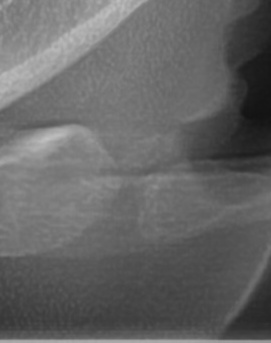

어금니 뒤 잇몸 부음 우선 원인부터 살펴보면 이러한 증상은 단순한 잇몸 염증에서부터 더 심각한 치주 질환이나 사랑니 문제까지 다양하게 발생할 수 있는데요. 보통 잇몸이 붓는 것은 세균 감염, 음식물 잔여물에 의한 자극, 치주 질환, 사랑니 문제 등이 원인이 되는 경우가 많으며 증상이 가벼울 때는 자연적으로 가라앉을 수도 있지만, 제대로 치료하지 않고 반복되는 잇몸 문제가 갈수록 진행된다면 염증이 심해지고 통증이 심해질 수 있고 잇몸이 주저 앉거나 심한 경우 치아가 흔들릴 수 있어서 원인을 정확하게 파악하고 적절한 치료를 받는 것이 중요하다고 볼 수 있어요

어금니 뒤 잇몸 부음의 문제는 사랑니가 원인이 되는 경우도 많은데 사랑니는 특히 현대인들의 경우 제대로 나오지 못하고 매복되는 경우가 많으며 완전히 나오지 않은 사랑니는 잇몸 속에서 자라면서 주변 잇몸을 자극할 수 있고, 일부만 노출되면 음식물이 끼면서 염증이 생기기도 하며 특히 어금니 뒤쪽 잇몸이 붓고 지속적으로 불편함을 느낀다면 사랑니로 인한 염증을 의심해 볼 수 있어요. 사랑니로 인한 문제의 경우 단순한 소염제나 구강 세정제로 해결되지 않고, 사랑니를 발치해야 잇몸 염증이 해결되는 경우가 많이 있어요

가장 주의해야 하는 문제 중에 치주염이 진행되면 어금니 뒤쪽뿐만 아니라 전체적인 잇몸이 약해질 수 있어요. 치주염은 치아를 둘러싸고 있는 조직이 손상되는 질환인데 특히 잇몸이 자주 붓거나 피가 나는 경우에는 치주염이 진행되고 있는 신호일 수 있기 때문에 단순한 잇몸 붓기로 넘기지 않는 것이 좋으며 치료를 받지 않으면 결국 치아를 지탱하는 뼈가 약해지고, 심한 경우에는 치아가 흔들리거나 빠질 수도 있었어요.